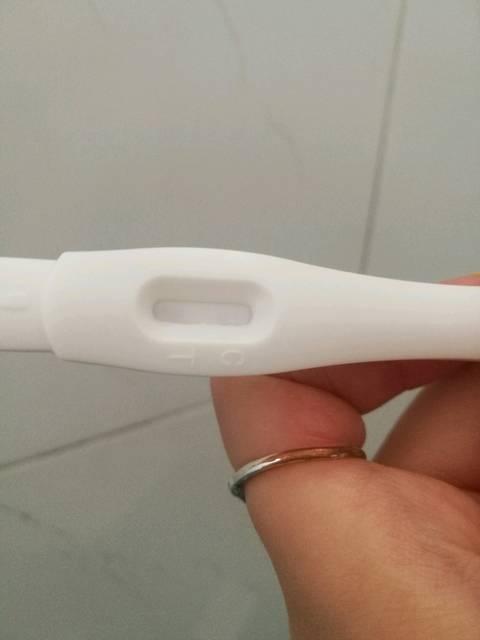

平时月经准时,当月经过期一周仍不见来者,应该首先意识到可能是怀孕。当务之急是去医院进行血HCG检测、尿HCG检测,B超检测来判断是否怀孕。其次避免影响胚胎分化和胎儿发育的各种危险因素。如:放射线、烟、酒、滥用药物、各种有毒物质,病毒感染,特别是风疹感染,该病在怀孕初期的畸形儿发生率可高达55—60%。

当然,不同人群的怀孕反应差异非常大,仅仅通过上述症状来确定自己是否怀孕是很不科学的,一定要到医院进行HCG尿检或者HCG血检、B超等检查,这样才能准确的判定自己是否怀孕,从而做出正确的处理